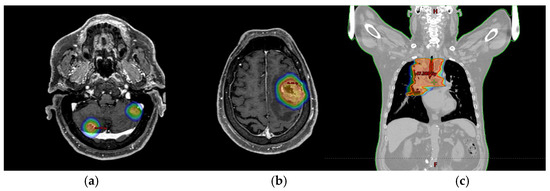

2. Case Report